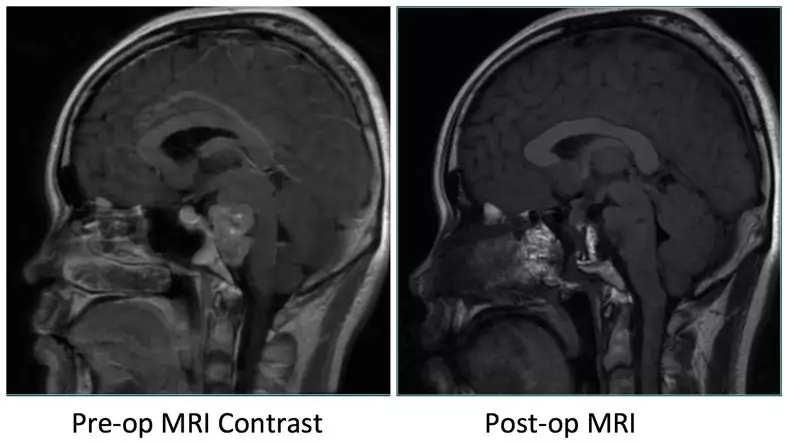

• MRI Images:Reveals occupying lesions in pre-pon cistern, tumor with a upper clivus extension imbedding into brainstem from anterior.  Part of clivus bone is erosion.

Pre-op MRI Contrast

Post-op MRI with contrast

Post-op MRI